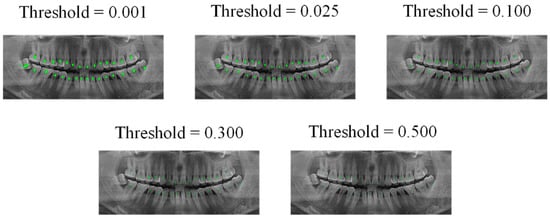

Subsequently, two deep learning models were trained using datasets A and B; both models were U-Net, and due to our hardware limitations, we set the batch-size to 1, the learning rate to 0.01, and the epochs to 9. Then, we input the 10 processed images into the model trained in dataset B to obtain 20 edge images with threshold values of 0.5 and 0.94, and used the channel stitching method to stitch these edge images with the semantic segmentation mask, to obtain 20 processed images. In the next step, the VIA tool was used to mark the central points of these 20 images, perform image augmentation, and mark it as dataset C. Dataset C was used for training the new U-Net model. The effects of the measured model at output thresholds of 0.001, 0.025, 0.1, 0.3, and 0.5, are shown in Figure 10.

Figure 10.

Output of teeth central point dataset under different thresholds.

Figure 10 indicates that if the image output is according to the default output threshold (0.5) of conventional semantic segmentation, the central point image cannot effectively express all object centers of the teeth. However, if the output threshold is set to very low levels, we often encountered adhesion of the object centers of the teeth; based on experience, we set the threshold of the central point output to 0.025, so that all centers can be expressed as much as possible, and they are also well separated.